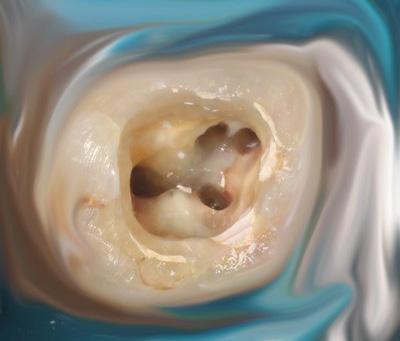

Imponerande bildkvalitet , djupskärpa och användarvänlighet

Patientkommunikation, kariesdiagnostik och dokumentation på högsta nivå

Kamerasystem från DÜRR DENTAL ger värdefull hjälp vid odontologiska behandlingar och ökar patientförståelse för dina behandlingsåtgärder. Kamerorna ger pålitligt stöd tack vare den smarta mekanismen med utbytbara huvuden: vid diagnos eller tidig upptäckt av karies samt vid plackvisualisering. Dessutom blir dina behandlingsrekommendationer ännu lättare att förstå för patienten. VistaCam imponerar med sin utmärkta bildkvalitet, djupskärpa och användarvänlighet.

Tack vare den steglösa autofokusfunktionen möjliggör Macro-bildtagningar till extraorala bildtagningar (HD CAM)

Briljant HD-bildkvalitet även i videoläge

Mjukvaruutvärdering för detektion av karieslesioner och visning av plack (Proof-utbytbart huvud)

Diagnoshjälpmedel vid approximalkaries utan strålbelastning (utbytbart Proxi-huvud)